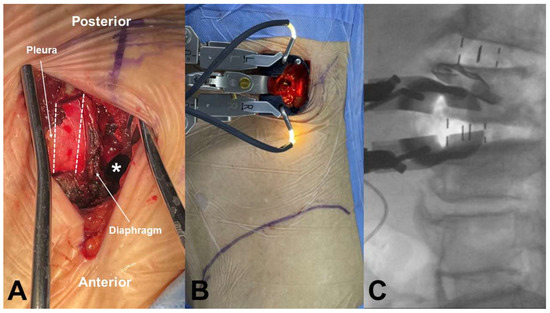

All surgical procedures were conducted by a single experienced spine surgeon (N.C.) following the original OLIF technique described by Hynes [1]. Under general anesthesia, patients were positioned in the right lateral decubitus posture at 90 degrees on a Jackson Spinal Surgery Table (Mizuho OSI, Union City, CA, USA). The exact lateral position was verified using AP and lateral fluoroscopic guidance with a C-arm. In the upper lumbar spine, the L1–2 (or L2–3) disc level was identified and marked under the C-arm. After palpating the ribs around the target level, a skin incision approximately 4 cm in length was made along the direction of the rib. If the surgical trajectory was obstructed by the rib cage, we performed partial resection of the 11th or 12th rib. Following this, the diaphragm was carefully retracted anteriorly to access the retroperitoneal space. The target disc was then exposed using the OLIF25 tubular retractor system (Medtronic Inc., Minneapolis, MN, USA) via a retroperitoneal antepsoas approach (Figure 1A,B).

Figure 1. OLIF approach at upper lumbar spine. (A) The retroperitoneal space was accessed by resecting the 11th rib (dotted line) without pleura laceration and retracting the diaphragm anteriorly (white asterisk; retroperitoneal space). (B) The tubular retractor was mounted at the L1–2 disc space. (C) Intraoperative fluoroscopic images of OLIF at L2–3, performed through the same incision after completing OLIF at L1–2.

Extensive discectomy and removal of the cartilaginous endplates were performed to prepare for OLIF cage insertion, with meticulous care taken to preserve the bony endplates. Contralateral annular release was performed using a blunt-tipped shaver with gentle hand tapping, followed by sequential trial insertions to distract the disc space. A lateral polyetheretherketone cage (Clydesdale; Medtronic Inc.) filled with autologous iliac bone and a demineralized bone matrix (Grafton; Medtronic Inc.) was inserted obliquely into the disc space and rotated orthogonally in the true lateral direction (Figure 1C). Under AP C-arm fluoroscopic guidance, the cage was advanced to the midline of the disc space in a press-fit manner. If a pleural laceration occurred during the anterior approach, a chest tube was placed after cage insertion. Following this, primary repair of the pleura was performed, and the muscles were closed layer by layer. Upon completion of the anterior procedure, the patient was repositioned into the prone position, and supplemental posterior pedicle screw fixation was performed using either an open or a percutaneous technique. In cases of severe central canal stenosis [11], in which the dural sac showed a homogeneous gray signal with no visible CSF or rootlets, additional laminectomy was carried out.